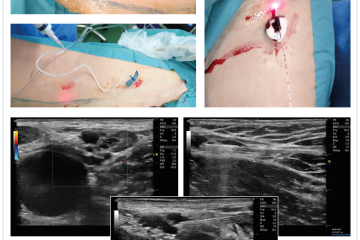

Obě kazuistiky jsou ukázkou situace, kdy dilatovaná LNVN by mohla být chybně považována za neovaskularizaci. Oba případy pak byly následně řešeny zcela ambulantní formou, pomocí endovenózních zákroků. Byla použita kombinace endovenózní termální laserové ablace v kombinaci s ultrasonograficky navigovanou pěnovou sklerotizací (obr. 6).